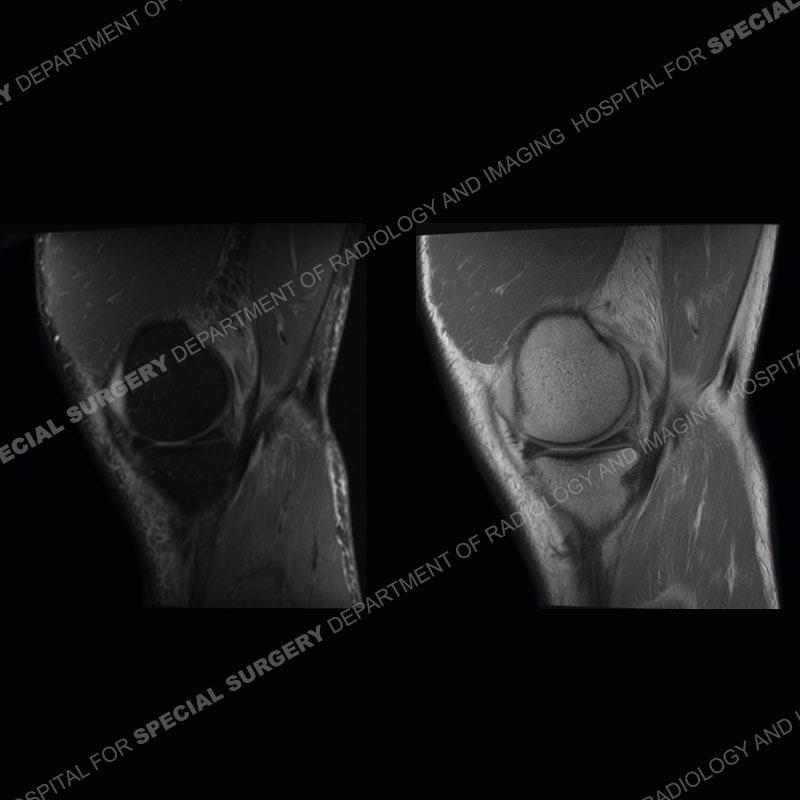

The radiographs show degenerative change of the medial compartment and a varus knee, but they are not germane to this case. No acute bony injury is present. The MRI shows edema of the posterior medial knee/soft tissue and a focal area of a partially disrupted low signal structure. The details are kept at a minimum in the findings of this case on purpose.

Diagnosis: Partial Disruption Medial Head Gastrocnemius (MHG)

The findings were kept purposefully vague as identifying the structures early on takes away a lot of the diagnosis. An uncommon entity and one of which we do not see a lot. Enthesopathic changes and tendinosis are seen as are distal MHG injuries, but proximal tears are rarely present. This case highlights a number of points. One, it almost always comes down to anatomy. Perhaps not a structure we normally spend too much time on, except save for diagnosing a Baker’s cyst, but knowing where this structure and all structures exist in all three planes is imperative. Second, when you think you are making a “call” or finding that you have never made before, step back and think is this just the abnormal presentation of a common pathology. That situation arises much more frequently. Third, if you look at it once, twice, and probably a third time and are confident in your odd or very rare diagnosis, stick to your guns. Especially, when it comes down to anatomic structures, the proof will be in the images.

Fourth, use all imaging planes and different pulse sequences to make your diagnosis. The edema highlighted in this case can be seen as the obscuration of fat on the PD images but is much easier to perceive as the high signal on the IR pulse sequences. The actual disruption of the MHG myotendinous junction is only able to be seen on the axial images. On the sagittal and coronal images, we get a sense something is wrong but hard to be exact. Lastly, when you look at a study and something just seems off (as I would say the sagittal and coronal images do with that dark band of tissue posteriorly), listen to yourself and go through the study slowly and meticulously. Most of the time you will find you were right, and something indeed is present.